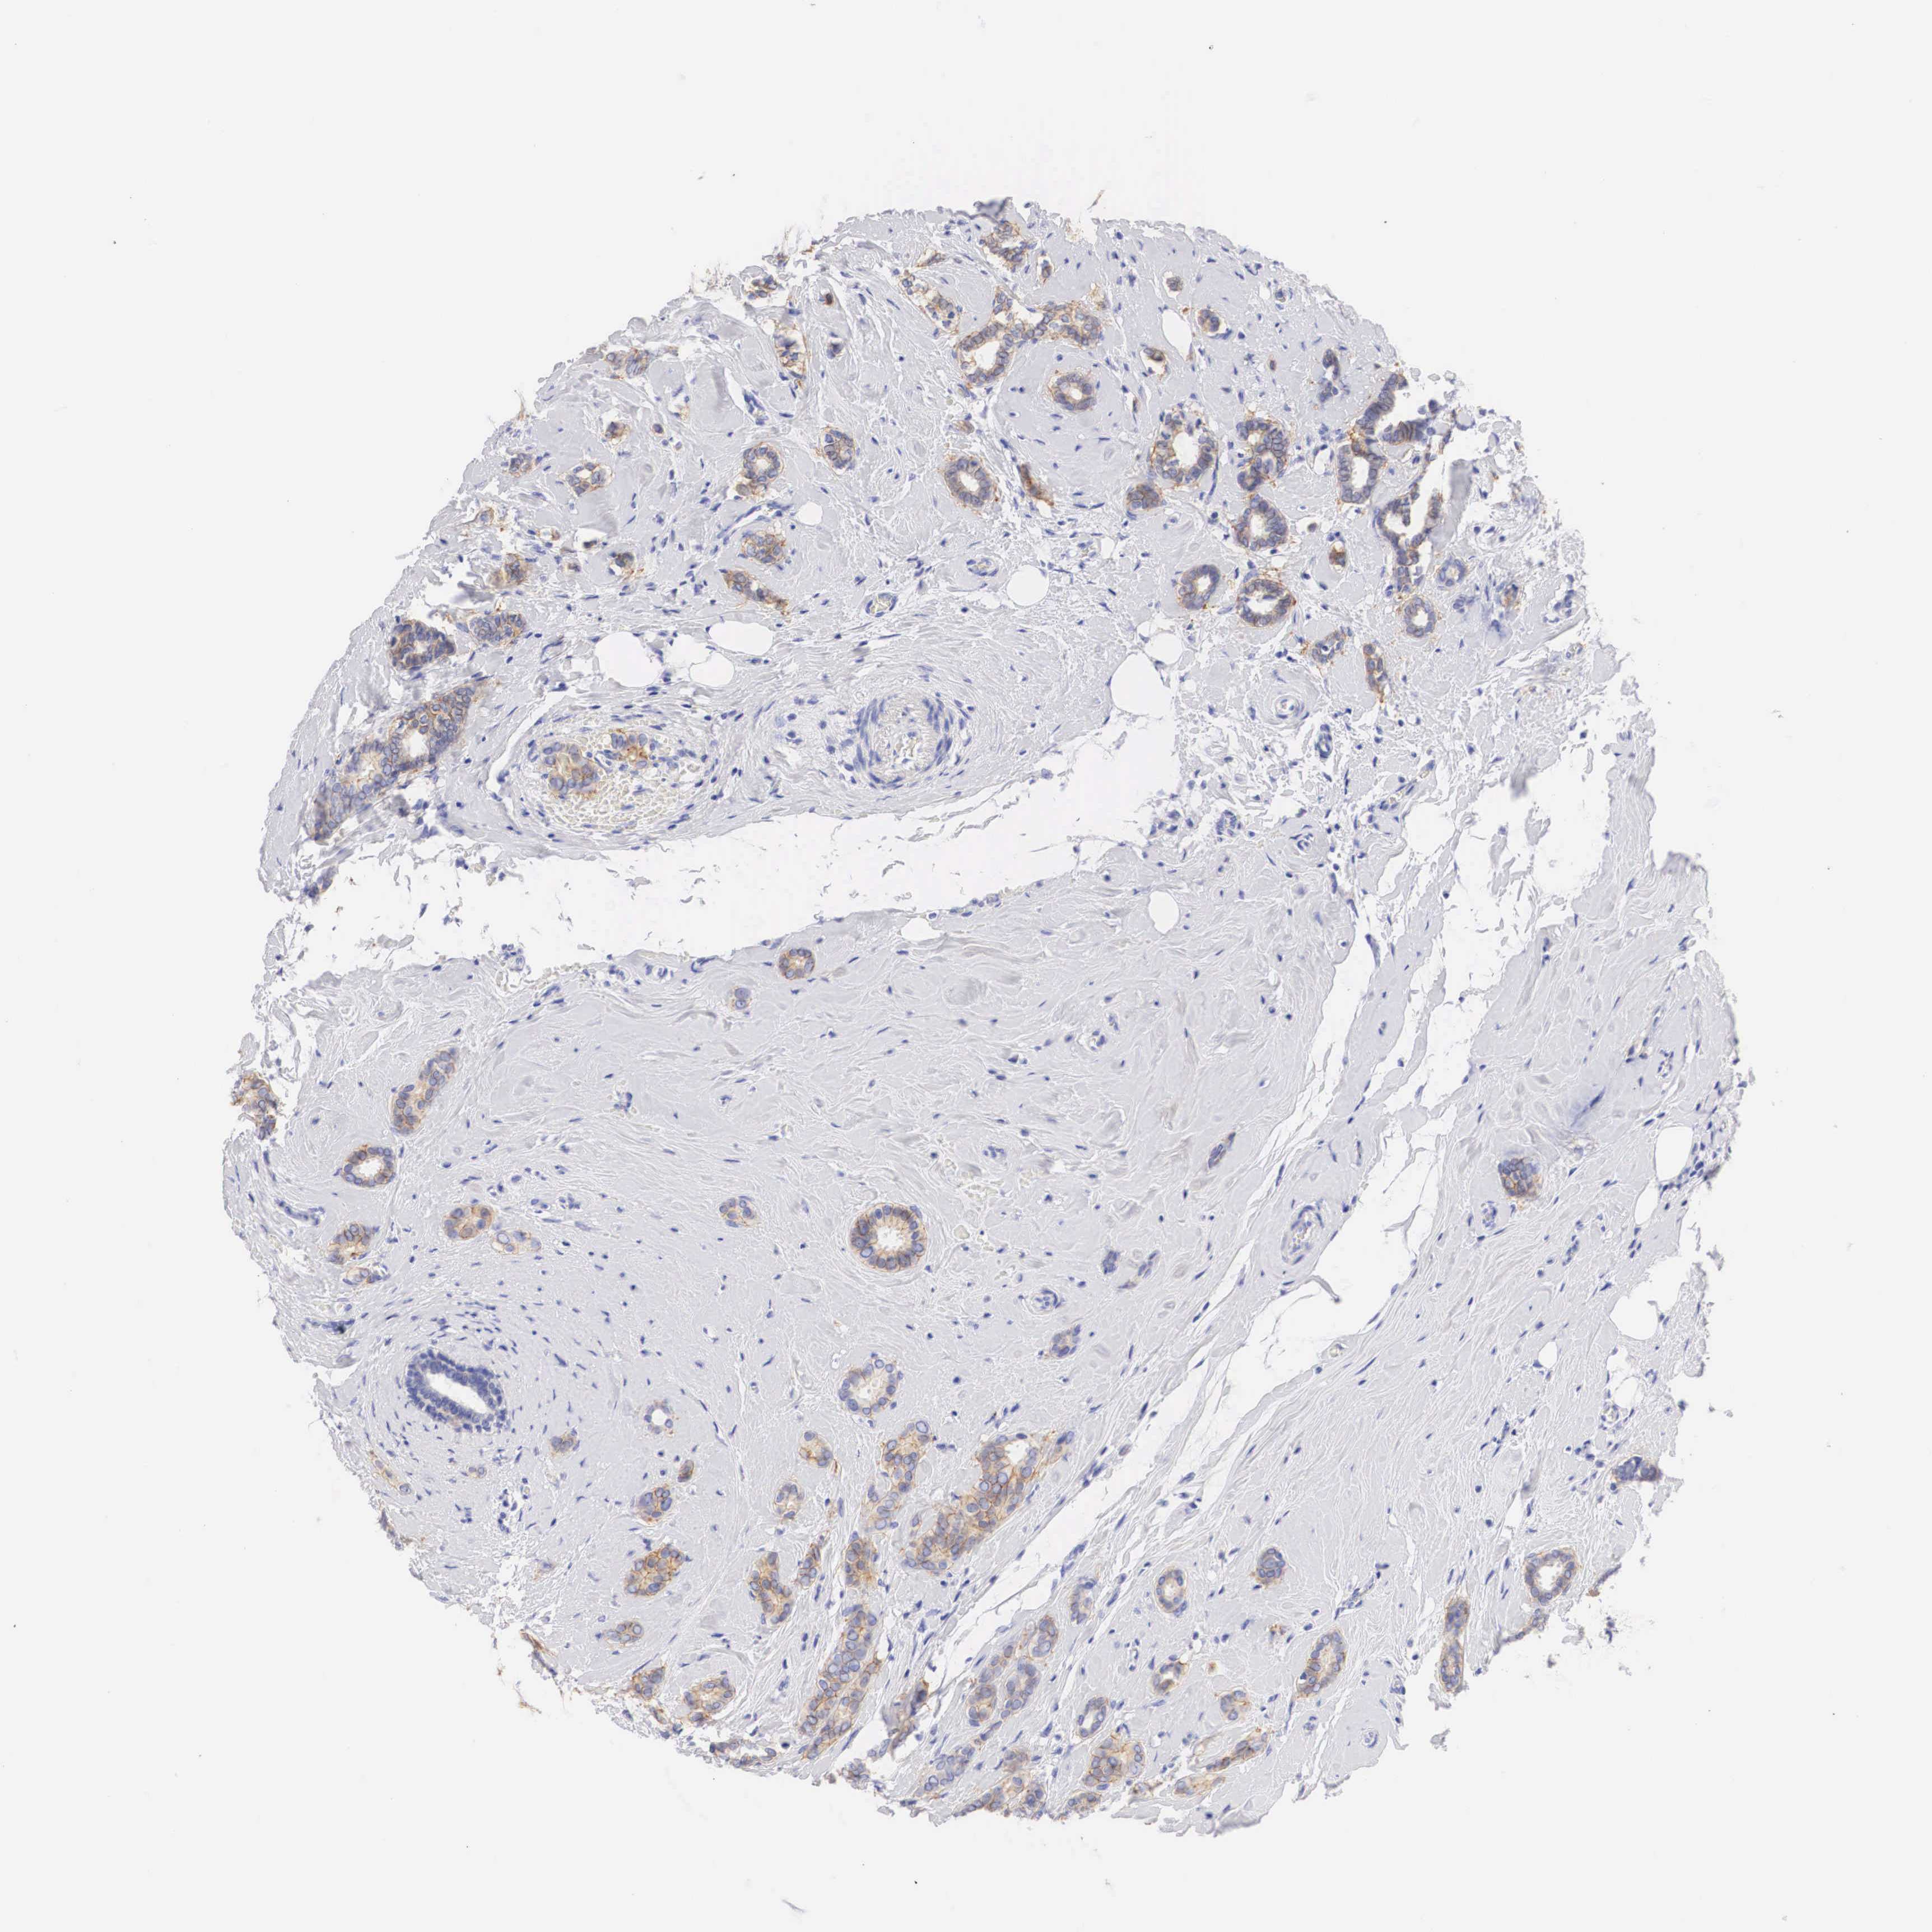

CANCER BREAST CANCER Show tissue menu

BRCA TCGA BRCA VALIDATION PROTEIN EXPRESSION

Breast cancer

Human cancer